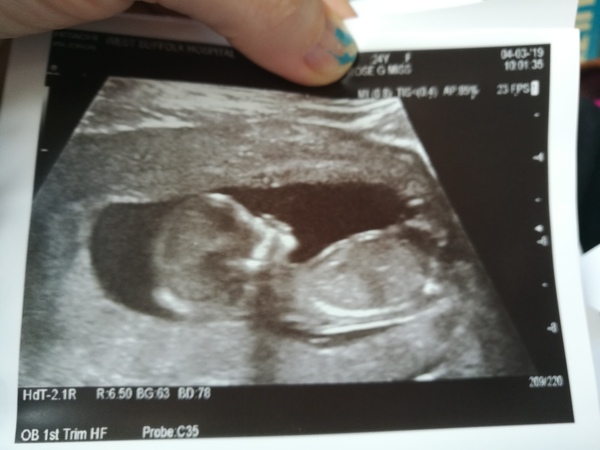

TwittleBee · 04/03/2019 14:54

Dating scan complete! All looks lovely! Been dated at 17.09.19 now rather than 19.09.19 as put at previous scans!

September 2019 Babies - Thread #3

TwittleBee · 04/03/2019 15:15

No sign of bleeding internally and actually was bleeding at time of the scan so they've put it down to an irritated cervix again!